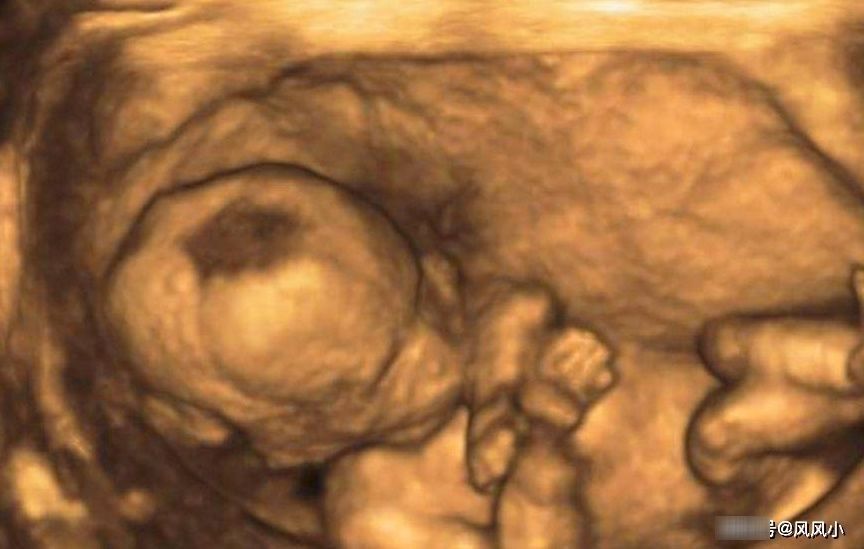

在做检查之前也要提前预约好,如果没有预约可能要排队,人少情况可能当天能检查,人多可能当天都无法检查,,对于怀孕的人来说太过于折腾了,搞不好还会影响肚子里的胎儿,所以做之前提前预约,免了排队的辛苦。做过四维的宝妈都应该知道,做这个时候宝宝的配合也是很重要的。宝妈也要提前准备点巧克力,补充体力。而且在宝妈吃饱后,宝宝活动也比较频繁,这样检查的比较全面。宝妈也要提前休息好,毕竟检查也是很费体力的,要是宝宝不配合的话可能还需要爬楼梯。四维彩超主要是为了看看宝宝是不是有畸形,或者脑积水之类的。大多数孕妈为了让自己放心都会选择去做的,这样对自己家庭和小孩都是有好处的。